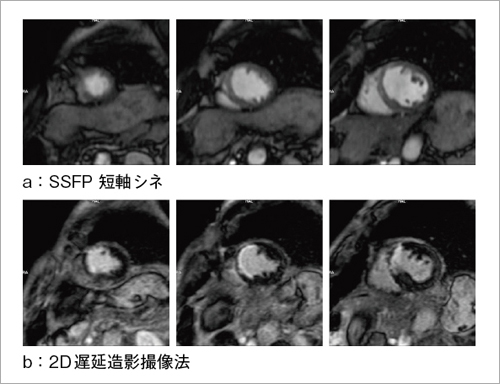

高い時間分解能を生かしたシネ撮像法による心機能解析や,造影剤投与後,十数分待って撮像することにより,心筋梗塞部位などを明瞭に描出できる遅延造影撮像法も良好な画像が得られる(図3)。さて,遅延造影撮像法においては,心筋の信号値がゼロ近くになるTI(Inversion Time)を,撮像時の条件設定で決定しなければならない。このとき,TIを変えながら複数の画像を撮像してTI値を決定する“TI-prep”機能を用いることで,設定すべきTI値を容易に求めることが可能となった(図4)。ここで重要なのは,インバージョンパルスによって反転された縦磁化が回復する際,実際の撮像では,撮像に用いるRFパルスによって,縦磁化の回復曲線が変形を起こすことである。これが原因となり,TI-prepで求めたTI値と実際の撮像でのTI値が異なる場合がある。そこで,遅延造影撮像のシーケンスそのものにTI-prep機能を適用することで,正しいTI値を容易に,かつ正確に求めることを実現している。

図4 TI-Prep

(画像ご提供:特定医療法人社団同樹会 結城病院様)